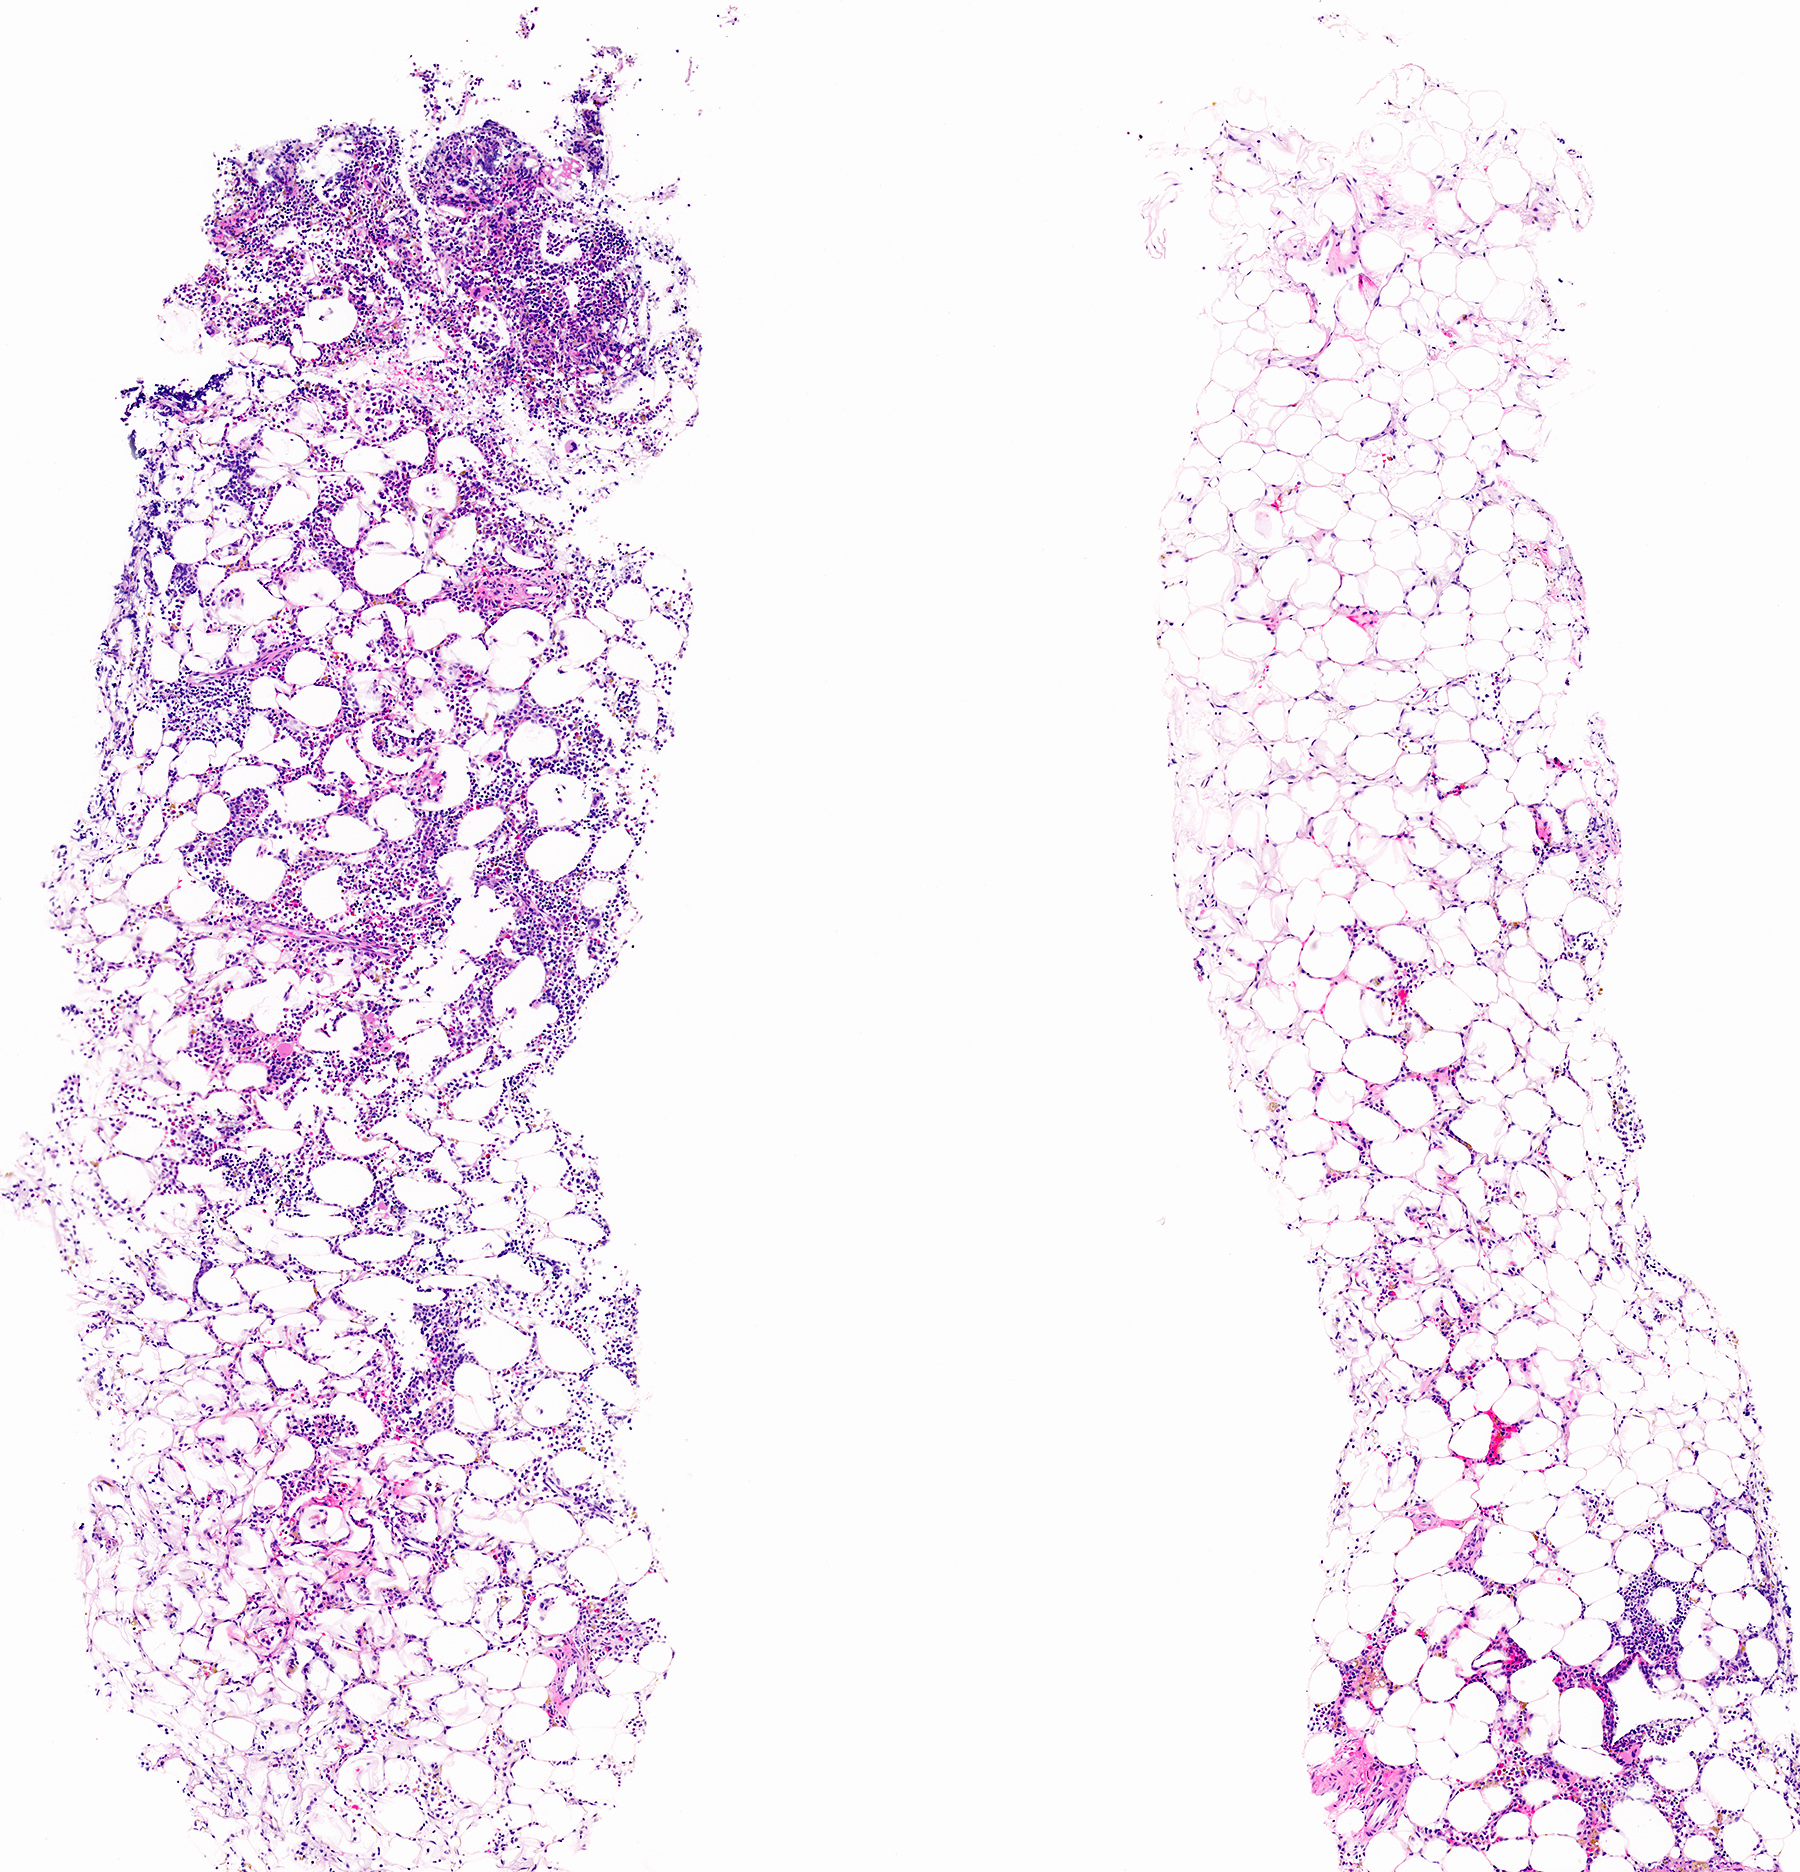

- Mixture of mature adipocytes and extramedullary trilineage hematopoietic cells with full maturation (similar to a hypercellular bone marrow) but often with a markedly increased number of megakaryocytes (Am J Surg Pathol 2006;30:838)

Microscopic (histologic) images

Contributed by Debra L. Zynger, M.D., Anil Parwani, M.D., Ph.D., O. Hans Iwenofu, M.D., Ph.D. and @ThatGlassTho on Twitter